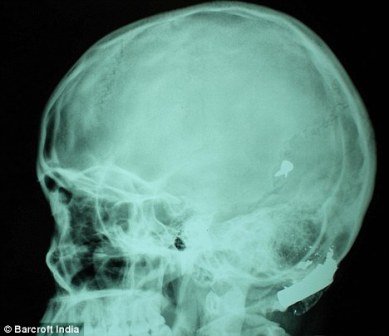

X光片显示子弹嵌在了赫娜的脑子里

其中一颗子弹击中她的左中耳,穿透了她的耳骨,然后击中头骨,嵌在了脑子里。另外两颗子弹分别击中她的右臂和心脏。印度Lok Nayak医院的医生称,赫娜能够康复完全是奇迹,她也足够幸运。她的主治医生称:“当我们看到她的情况时,被吓了一跳,幸运的是她活了下来。”

这颗子弹没有损坏大脑中控制身体机能的部分。尽管赫娜的手术很成功,但医生表示,她还有出现感染和并发症的可能。子弹毁掉了她的中耳,可能导致她耳聋。加拿大华人网 http://www.sinoca.com/